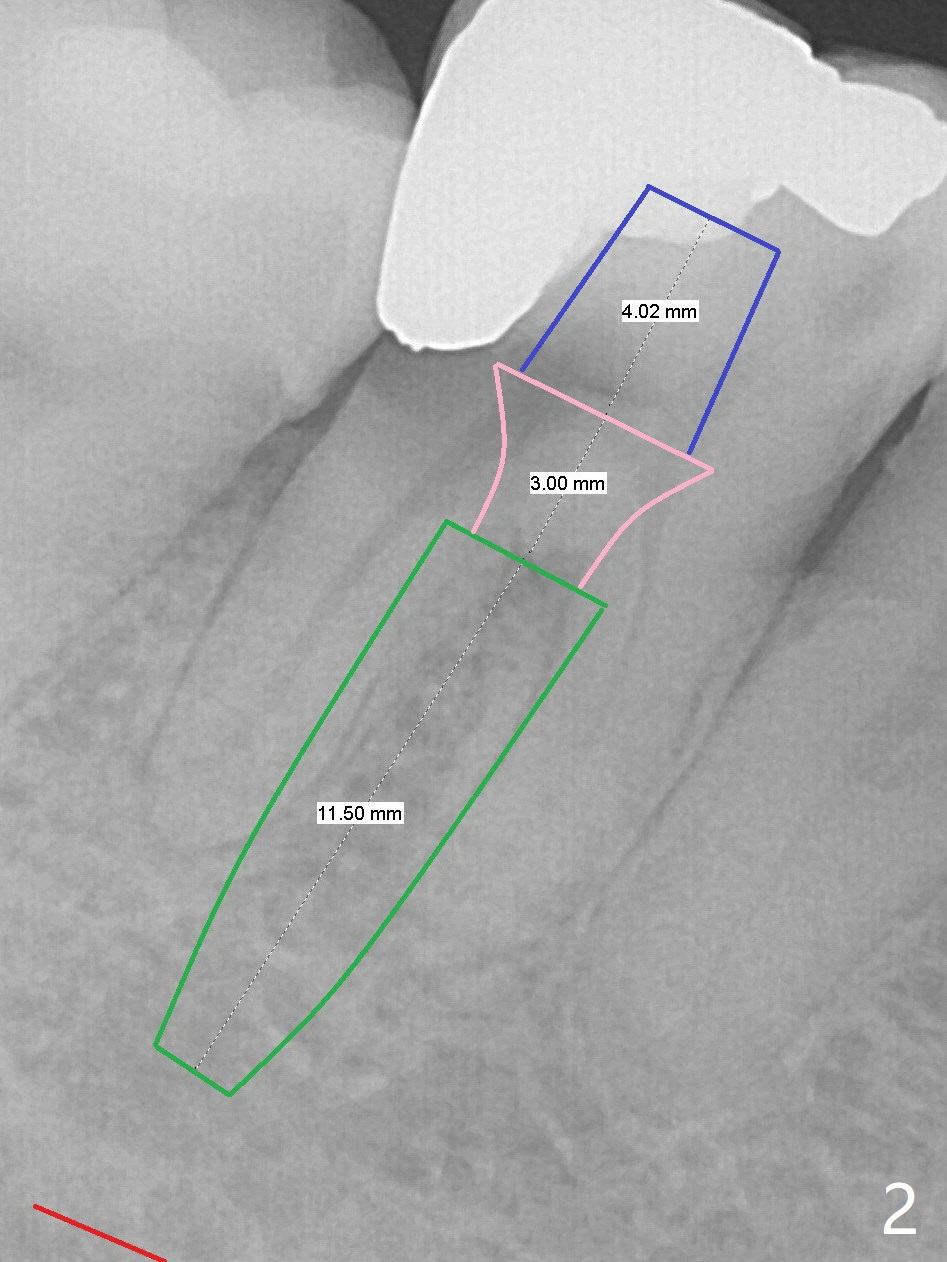

A 39-year-old woman has severe toothache associated with #30 subgingival caries (Fig.1 * distolingual). To reduce buccal plate perforation, a 4.5x11.5 mm implant will be placed (Fig.2 (bone height 15 mm). Take PA after parallel pin to make sure that blood supply to the tooth #29 is not compromised. For easy impression later, a temporary abutment will be used for immediate provisional so that a large soft tissue hemisphere is created. A cementation abutment is estimated to be 6.5x4(3) mm. Schedule SRP after implant placement (Fig.1). In fact the patient declines implant placement and accepts socket preservation (Fig.3 (*: Vanilla Graft)) because of history of hemorrhage associated with #19 extraction (Fig.4).